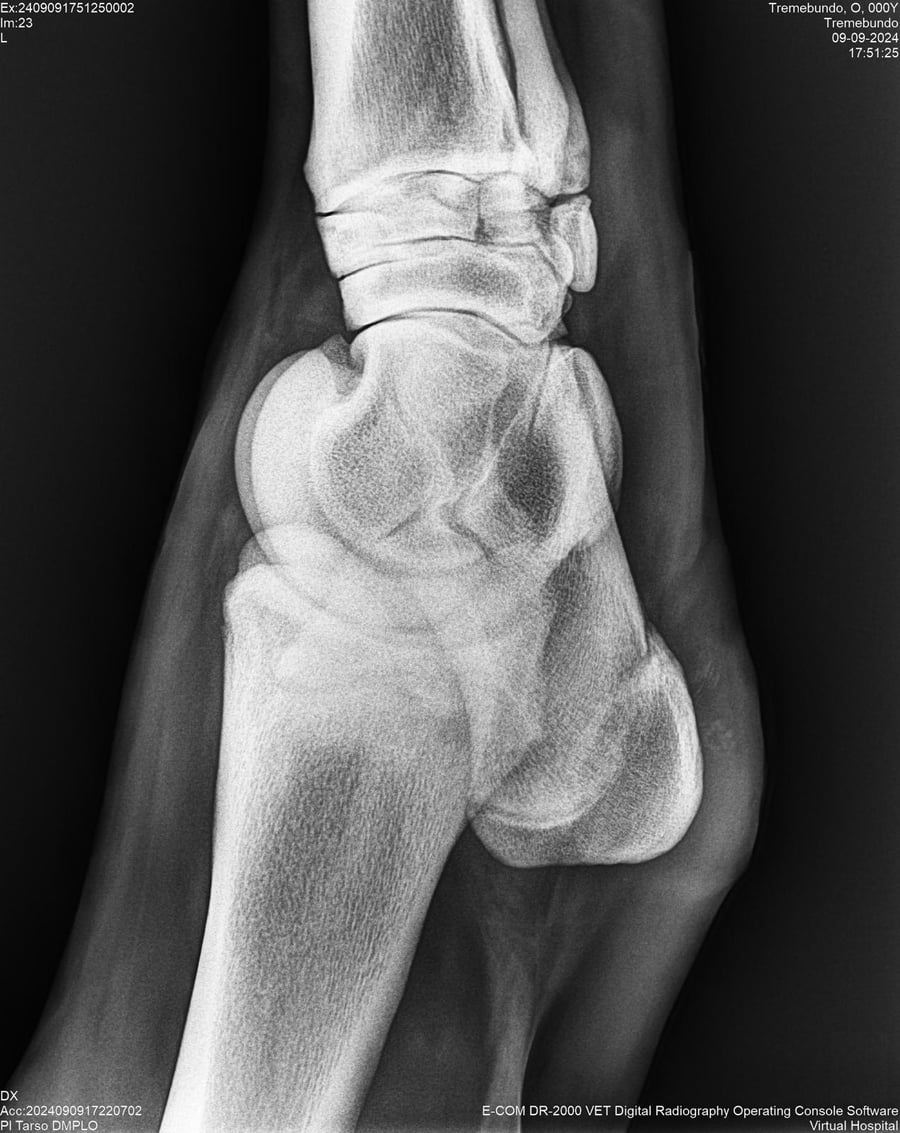

LOTE 37, TREMEBUNDO

Generacion 2022